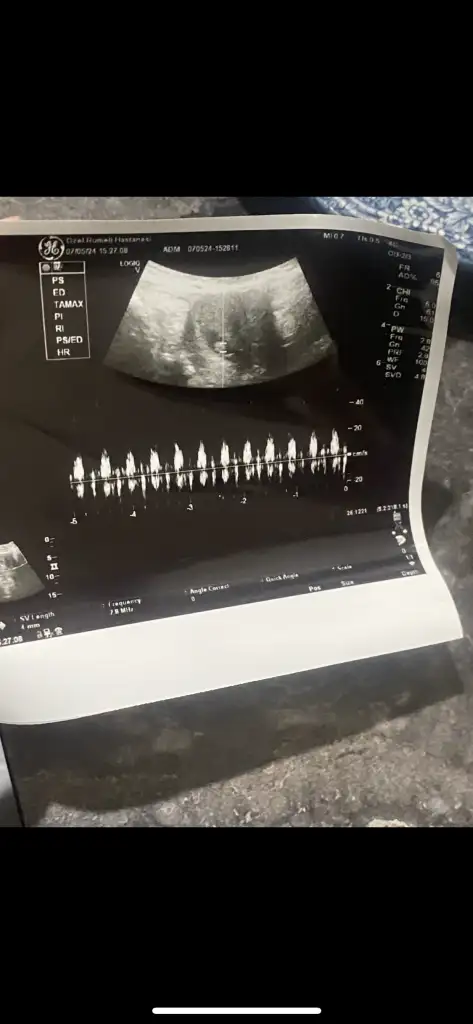

Biri 7haftalık diğeri 13haftalık

• IMG_0823.webp

• 5C0257EA-563C-41CD-970C-7A1AB6332457.webp